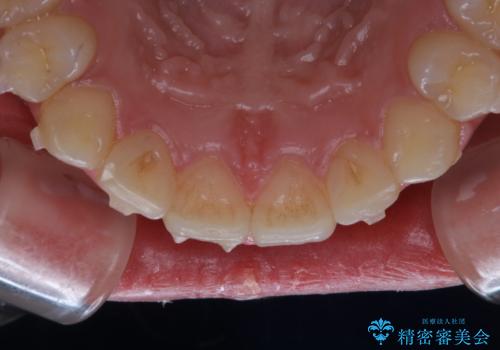

インビザライン中にステインの除去

- インビザラインでのマウスピース矯正中の方で、歯の表面のステインをきれいに取りたいとのことでした。PMTC60分コースを行いました。

PMTC(保険外治療)は、毎日の歯磨きで落としきれない汚れや、コーヒ、紅茶・タバコのヤニなどの着色も除去します。目には見えない歯と歯の間・歯肉の境目・インビザライン中はアタッチメント周囲などに残っているプラーク(歯垢)もしっかり取り除きます。PMTCでは専門的な機械や材料を使用して、徹底的に汚れを除去するため、虫歯・歯周病・口臭予防などにつながります。

またPMTCを行うことで、ご自身本来の歯の色になり自然な明るさになります。